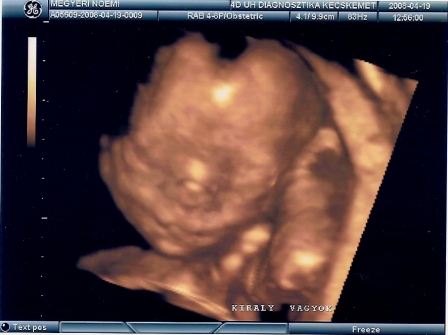

Ma voltunk gen. UH-on. Kép

A kisfiúnk.